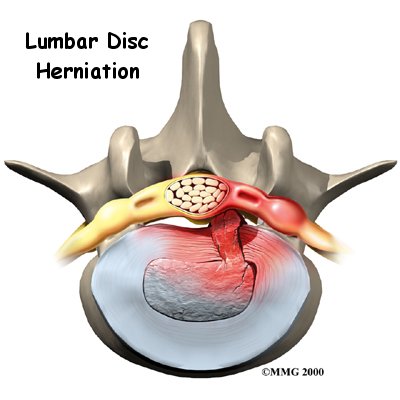

Herniation occurs when the nucleus in the center of the disc pushes out of its normal space. The nucleus presses against the annulus, causing the disc to bulge outward. Sometimes the nucleus herniates completely through the annulus and squeezes out of the disc.

Although daily activities may cause the nucleus to press against the annulus, the body is normally able to withstand this pressure. However, as the annulus ages, it tends to . It is repaired with scar tissue. This process is known as degeneration. Over time, the annulus weakens, and the nucleus may begin to herniate (squeeze) through the damaged annulus. At first, the pressure bulges the annulus outward. Eventually, the nucleus may herniate completely through the outer ring of the disc.

Although daily activities may cause the nucleus to press against the annulus, the body is normally able to withstand this pressure. However, as the annulus ages, it tends to . It is repaired with scar tissue. This process is known as degeneration. Over time, the annulus weakens, and the nucleus may begin to herniate (squeeze) through the damaged annulus. At first, the pressure bulges the annulus outward. Eventually, the nucleus may herniate completely through the outer ring of the disc.

Vigorous, repetitive bending, twisting, and lifting can place abnormal pressure on the shock-absorbing nucleus of the disc. If great enough, this increased pressure can injure the annulus, leading to herniation.

A lumbar disc can also become herniated during an acute (sudden) injury. Lifting with the trunk bent forward and twisted can cause a disc herniation. A disc can also herniate from a heavy impact on the spine, such as falling from a ladder and landing in a sitting position.

Herniation causes pain from a variety of sources. It can cause mechanical pain. This is pain that comes from the parts of the spine that move during activity, such as the discs and ligaments. Pain from inflammation occurs when the nucleus squeezes through the annulus. The nucleus normally does not come in contact with the body's blood supply. However, a tear in the annulus puts the nucleus at risk for contacting this blood supply. When the nucleus herniates into the torn annulus, the nucleus and blood supply meet, causing a reaction of the chemicals inside the nucleus. This produces inflammation and pain. A disc herniation may also put pressure against a spinal nerve. Pressure on an irritated or damaged nerve can produce pain that radiates along the nerve. This is called neurogenic pain.